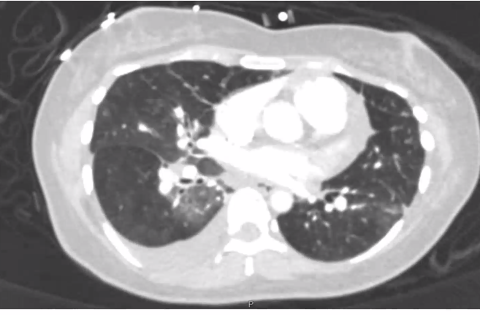

Lots of mosaic attenuation!

In summary: 36W with subacute worsening dyspnea on exertion, CT with mosaic attenuation, significant RV hypertrophy and dilation, VQ scan suspicious for CTEPH but PAgram negative, RHC with severe pre-capillary PH - mPA 90, PCWP 9, serology notable for slightly low vWF, weak + Scl

Whoops - seem to have accidentally started a new thread for the rest of the case. Case continues with the remainder of the HPI in image below, followed by CT scan here: